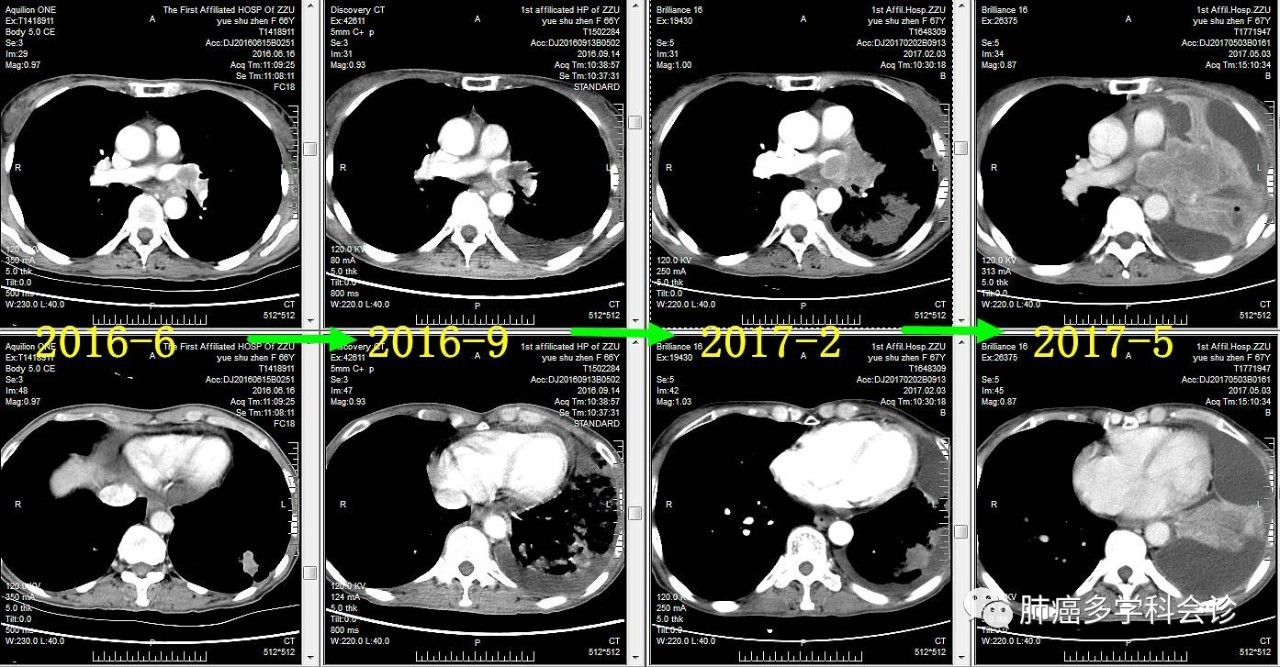

●2014.01 ~ 2016.03 口服易瑞沙获部分缓解,服药共2年余后因疾病进展而停用。以下是治疗过程中胸部肿瘤CT图像的变化:

以下为2016年6月到2017年5月期间,胸部肿瘤发展过程中CT所见:

微信图片_20170523115520.jpg于2017年5月,第三次 CT 引导下肺部肿瘤穿刺活检,病理报告:小细胞癌。微信图片_20170523115524.jpg